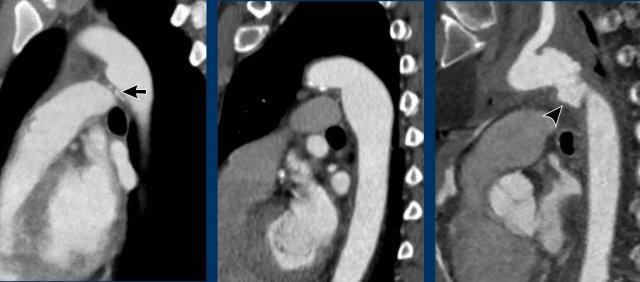

Hình ảnh

Nhĩ trái giãn.

Có huyết khối trong tiểu nhĩ trái (mũi tên) lan rộng về phía nhĩ trái (đầu mũi tên).

Tại tiểu nhĩ trái, thường gặp khó khăn trong chẩn đoán phân biệt hình ảnh giữa huyết khối và hiện tượng ngấm thuốc không hoàn toàn do dòng chảy chậm, đặc biệt khi chụp ở thì thuốc sớm.

Vấn đề này có thể được giải quyết bằng cách chụp CT ở thì thuốc muộn hơn hoặc chụp ở tư thế nằm sấp.

Siêu âm tim qua thực quản được coi là tiêu chuẩn vàng.

Xảo ảnh dòng chảy chậm trong tiểu nhĩ trái, với hình ảnh ngấm thuốc không hoàn toàn của tiểu nhĩ trái ở thì sớm nhưng lấp đầy hoàn toàn ở thì thuốc muộn hơn.